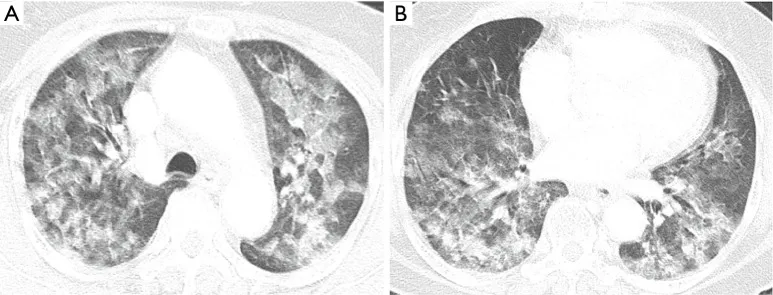

TK płuc u osoby z ARDS, masywne zmiany niedodmowo-zapalne.

Ryc. C – przekrój TK, na którym, aż widać, że coś jest „nie tak”. Miąższ płuca powinien być powietrzny, a w TK jawić się jako czarne plamki. Jednak nie tutaj, gdzie wszystko jest jakby zalane mlekiem. Zdjęcia A dotyczy płatów górnych. Natomiast B płatów dolnych. Pokazuje to zajęcie praktycznie całych płuc.